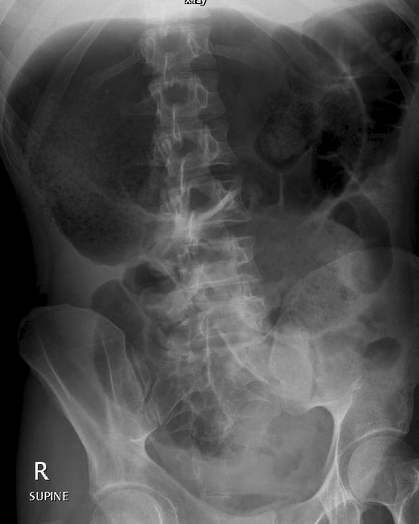

Volvulus du Sigmoïde

- Sur dolicho-sigmoïde ++

- Pointe jusque dans le pelvis (sauf si haut)

- Perte d’haustrations

- Coffe Bean Sign

- Dilatation du colon transverse et descendant

Volvuls du caecum

- Sur caecum mobile++

- Ne pointe pas jusque dans le pelvis

- Haustrations Preservées

- Foetus Sign

- Collapsus du colon transverse et descendant, dilatation des anses greles